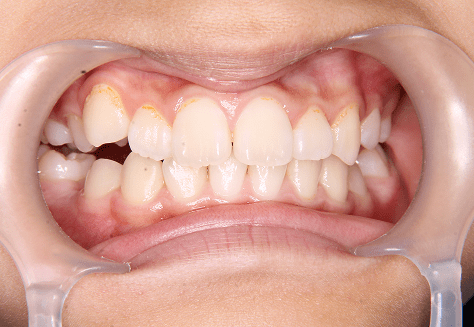

M.H

治療前

治療後

主訴

前歯が出ている。下の歯並びが特に気になる。奥歯でしっかり噛めない。

診断

上顎前突・叢生・シザーズバイト

年齢/性別

20代/男性

抜歯部位

下顎両側大三大臼歯(口腔外科にて)

上顎両側第一小臼歯・下顎左側側切歯

(当院にて5,500円×3) -

使用装置

上下エッジワイズ→インビザライン(PBM使用)

保定装置

上下ビベラリテーナー

料金

初回資料採得・・・・・・・30,000円

診断料・・・・・・・・・・33,000円

動的治療終了時資料採得・・5,500円 -

基本料金

880,000円

診察料金

5,500円×44回

治療期間

3年6カ月